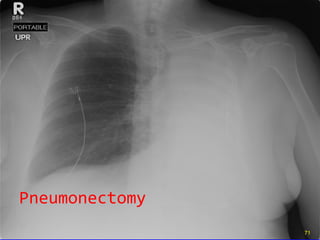

Pneumonectomy

Pneumonectomy Entire mediastinum shifted left, indicating  volume loss Opacified left hemithorax Trachea shifted left, indicating  volume   loss